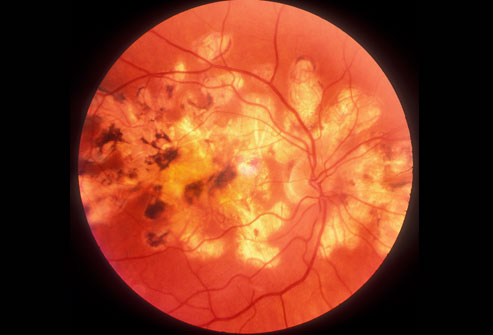

三分之一的糖尿病患者甚至不知道自己患了糖尿病。糖尿病会引起心脏病、中风、肾病、因视网膜血管受损导致失明(如图所示)和其他严重问题。你可以通过饮食、运动、减肥、和药物治疗来控制糖尿病,特别是在你发现得及时的情况下。2型糖尿病是常见的疾病。1型糖尿病的患者通常是儿童和年轻人。